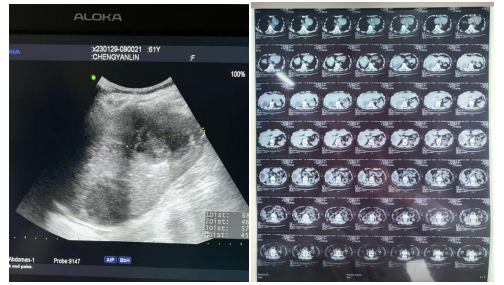

患者超声及CT检查影像

61岁的陈婆婆家住新洲,因右上腹持续性疼痛发热10天,伴有畏寒、高热,在当地医院行补液抗炎治疗,效果不佳,于1月29日到湖北省第三人民医院(省中山医院)阳逻院区就诊。经完善相关检查,超声检查提示:肝内多发无回声区(考虑肝脓肿)。得知检查结果后,陈婆婆及家属说出自己的顾虑:病痛难受、年龄大、术后伤口愈合迟缓、费用受限、家属不方便照顾等,经过普外科、超声影像科、麻醉科多学科会诊,在两院区一体化管理、学科深度融合的背景下,硚口本部超声影像科主任刘琨秉承着对专业的精益求精和不断创新精神和对病人减少创伤、减轻痛苦的原则,为陈婆婆制定了超声引导下肝脓肿穿刺引流方案。